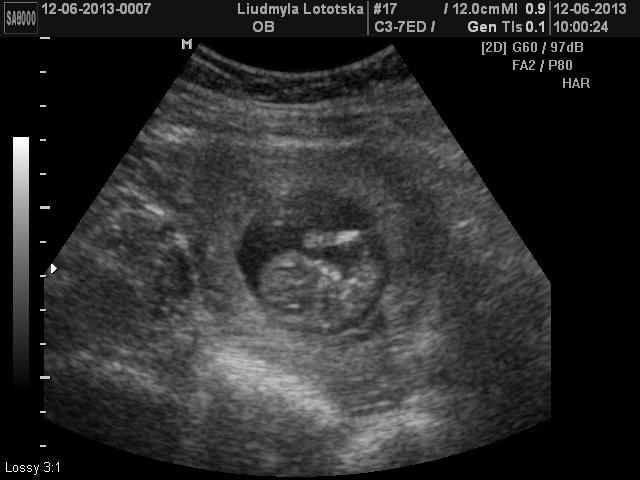

Зашли в кабинет,я легла,муж сел рядом. Когда узистка приклала только датчик наши сокровеща лежала один к одному попами)))потом когда начали все измерять и я увидила как они там пинаються и ручками машут меня поперло- слезы радости было не удержать...на мужа я вообще не смотрела))...Одного малыша хорошо померяли,а вот второй!!!....ух))))....кувыркался и не давал себя посмотреть)Но все таки все получилось,чему мы были очень рады)))....Кстати вот на этого хулигана сказали что будет мальчик!))

Ну и покажемся вам,мои дорогие: